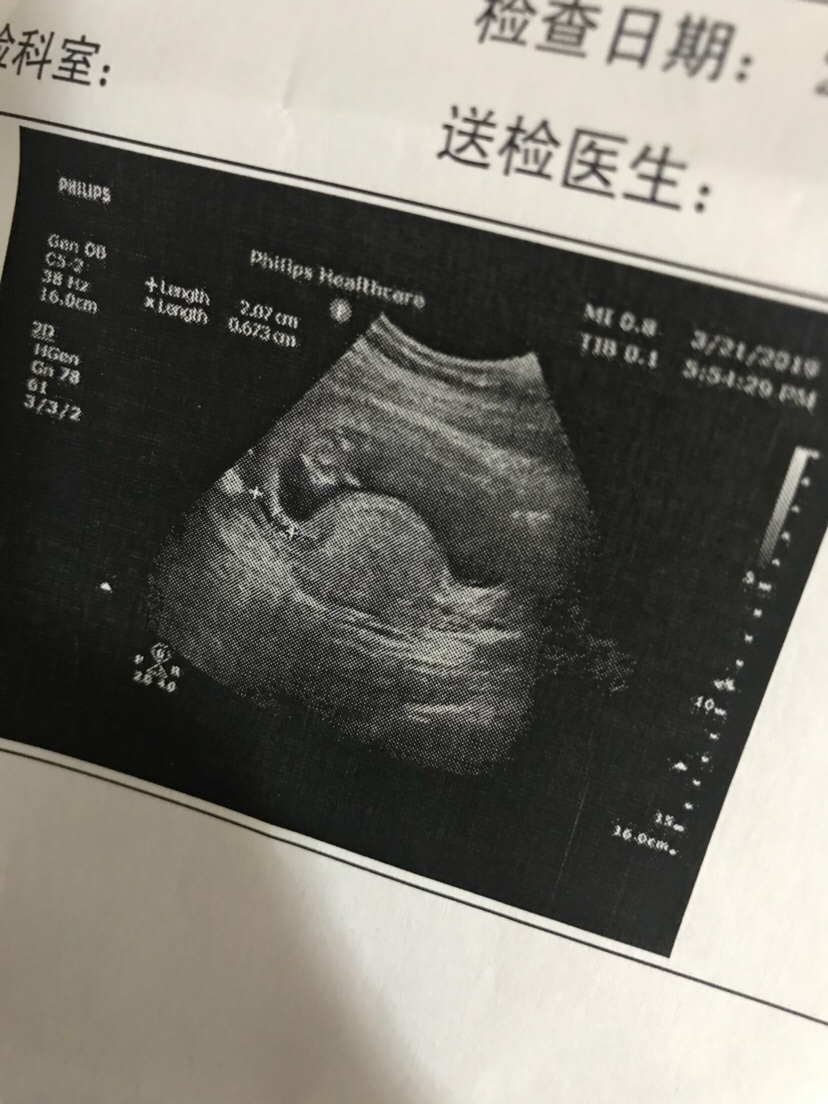

孕30周+0天

孕33周+4天

孕15周+6天

孕38周+3天